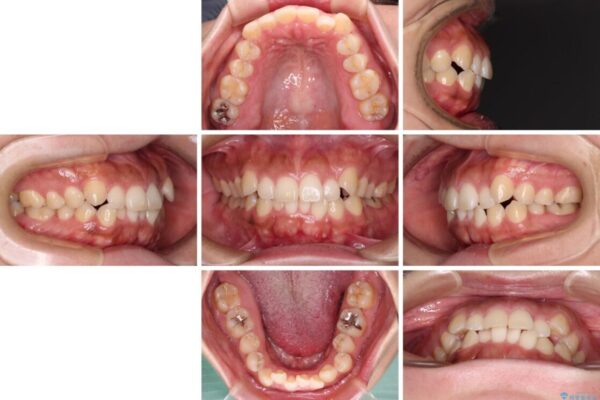

前歯の叢生と八重歯を気にして来院された患者様です。

目立たない装置を希望とのことで、インビザラインにて矯正治療を行うこととしました。

インビザライン単体で改善することも可能ですが、八重歯とその後方にある歯列を確実移動させないと、上下正中がずれてしまう可能性があります。

インビザライン単体での治療ではなく、カリエール・ディスタライザーという補助装置を併用して、より確実性を上げることとしました。

補助装置で八重歯を解消しながら、並行してインビザラインで歯列を整えることとしました。

治療前

• 【モニター】カリエール・ディスタライザーを併用した八重歯のインビザライン矯正 治療前画像